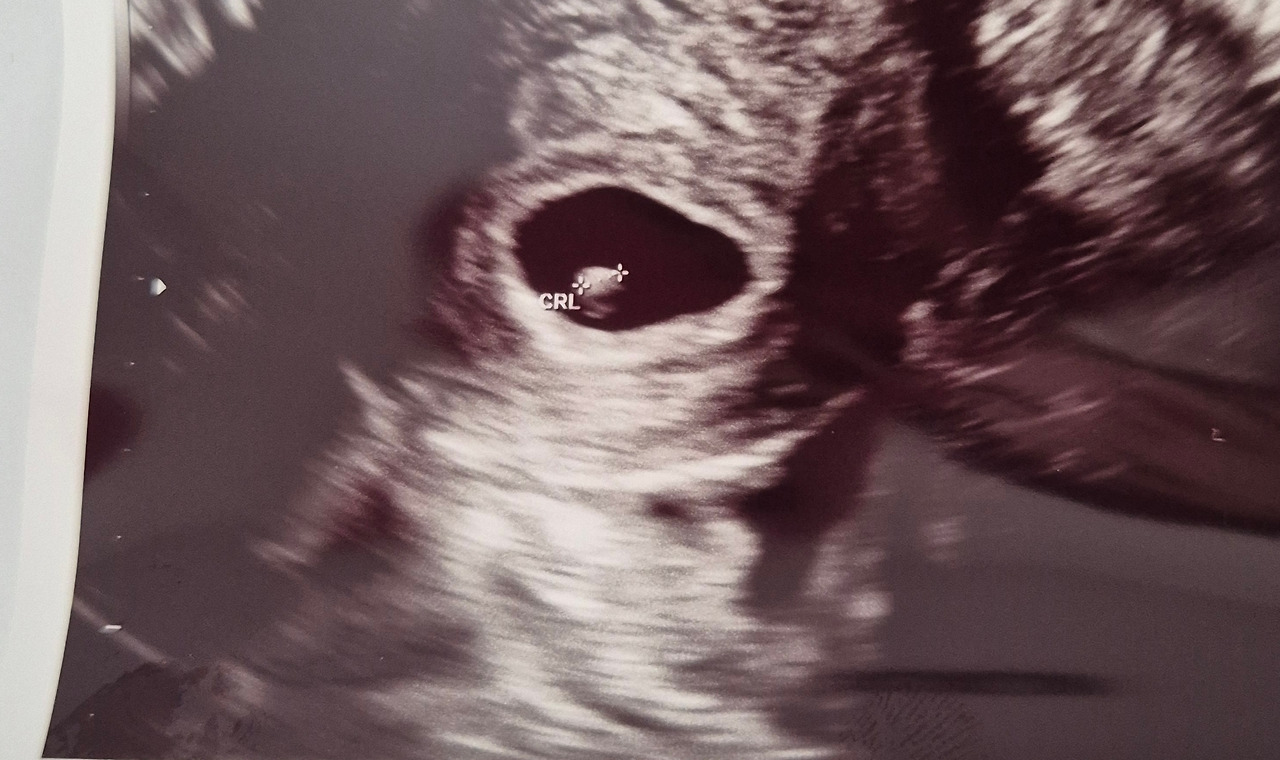

임신 6주 5일 차. 내 안에 작은 생명이 자라고 있다는 사실이 가끔은 실감 나지 않는다. 그런데 이 아이의 태명을 "토토"라고 지은 순간만큼은 너무나 자연스러웠다. 토토처럼 사랑스럽고 특별한 존재가 다시 내 인생에 찾아온 것 같았으니까.

CRL(태아 크기) 0.24cm